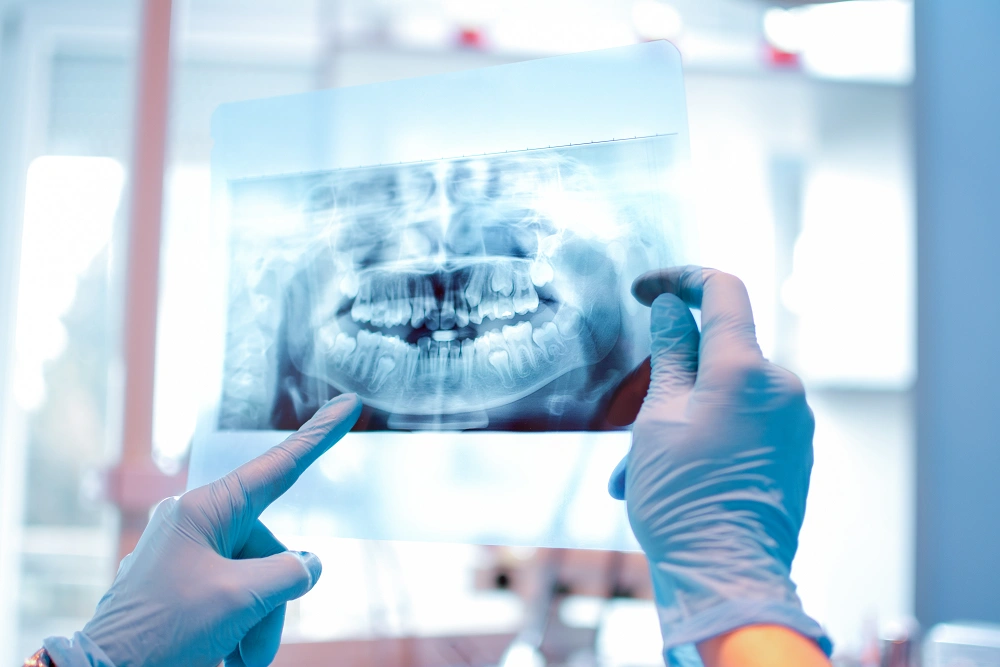

تصویربرداری دقیق و به موقع دندانها یکی از مهمترین ابزارهای دندانپزشکان برای پیشگیری و تشخیص مشکلات دهان و دندان است. تکنیک بایت وینگ به عنوان یک روش رادیوگرافی تخصصی، امکان مشاهده پوسیدگیهای بین دندانی، تحلیل استخوان و وضعیت ترمیمها را فراهم میکند، مواردی که با معاینه معمولی قابل تشخیص نیستند. این تکنیک نه تنها باعث افزایش دقت تشخیص میشود، بلکه به طراحی درمانهای پیشگیرانه و کاهش نیاز به مداخلات پیچیده کمک میکند.

تکنیک بایت وینگ یکی از روشهای رایج رادیوگرافی در دندانپزشکی است که به دندانپزشکان اجازه میدهد تا سطح بین دندانها و استخوان اطراف آنها را به دقت بررسی کنند. این تکنیک معمولا برای تشخیص پوسیدگی بین دندانی، تحلیل استخوان و مشکلات لثه استفاده میشود و در تشخیص زودهنگام بسیاری از مشکلات دهان و دندان بسیار موثر است.

تصویربرداری با تکنیک بایت وینگ ابزار قدرتمندی برای دندانپزشکان هستند تا مشکلات دهان و دندان را با دقت بالا تشخیص دهند. یکی از اصلیترین کاربردهای این تصاویر، بررسی پوسیدگی بین دندانی است که معمولا با معاینه بالینی قابل مشاهده نیست. پوسیدگیها در تصاویر بایت وینگ به شکل مناطق تاریک بین دندانها ظاهر میشوند و دندانپزشک میتواند عمق و شدت پوسیدگی را تعیین کند. این اطلاعات به طراحی درمان دقیق و به موقع کمک میکند.